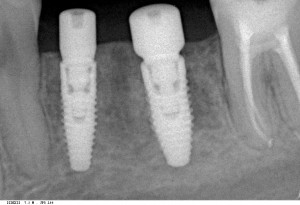

шмидт2   шмидт1

Снимок слева сделан сразу после операции, а справа — через 4 месяца, на этапе установки формирователей десны.